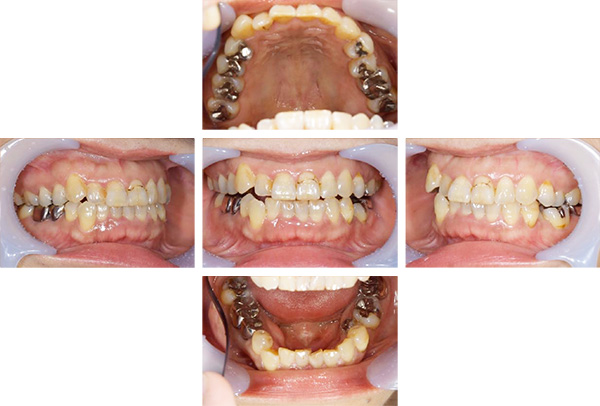

インレー症例

治療前

治療後

治療期間 8回(2ヶ月)

費用 ・セラミックインレー9本

合計:495,000円

治療リスク・副作用 ・詰め物、被せ物をする時は自分の歯を削ることになります

・歯ぎしり・食いしばりが強い方は、セラミックが割れてしまうことがあります。